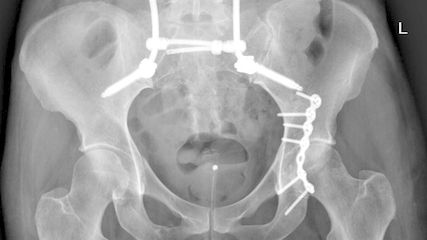

Die Indikationsstellung und Wertigkeit der lumbopelvinen Stabilisierung

Die lumbopelvine Stabilisierung bietet als etabliertes Verfahren eine hohe biomechanische Stabilität. In diesem Artikel werden anhand der aktuellen Literatur und Empfehlungen die ...